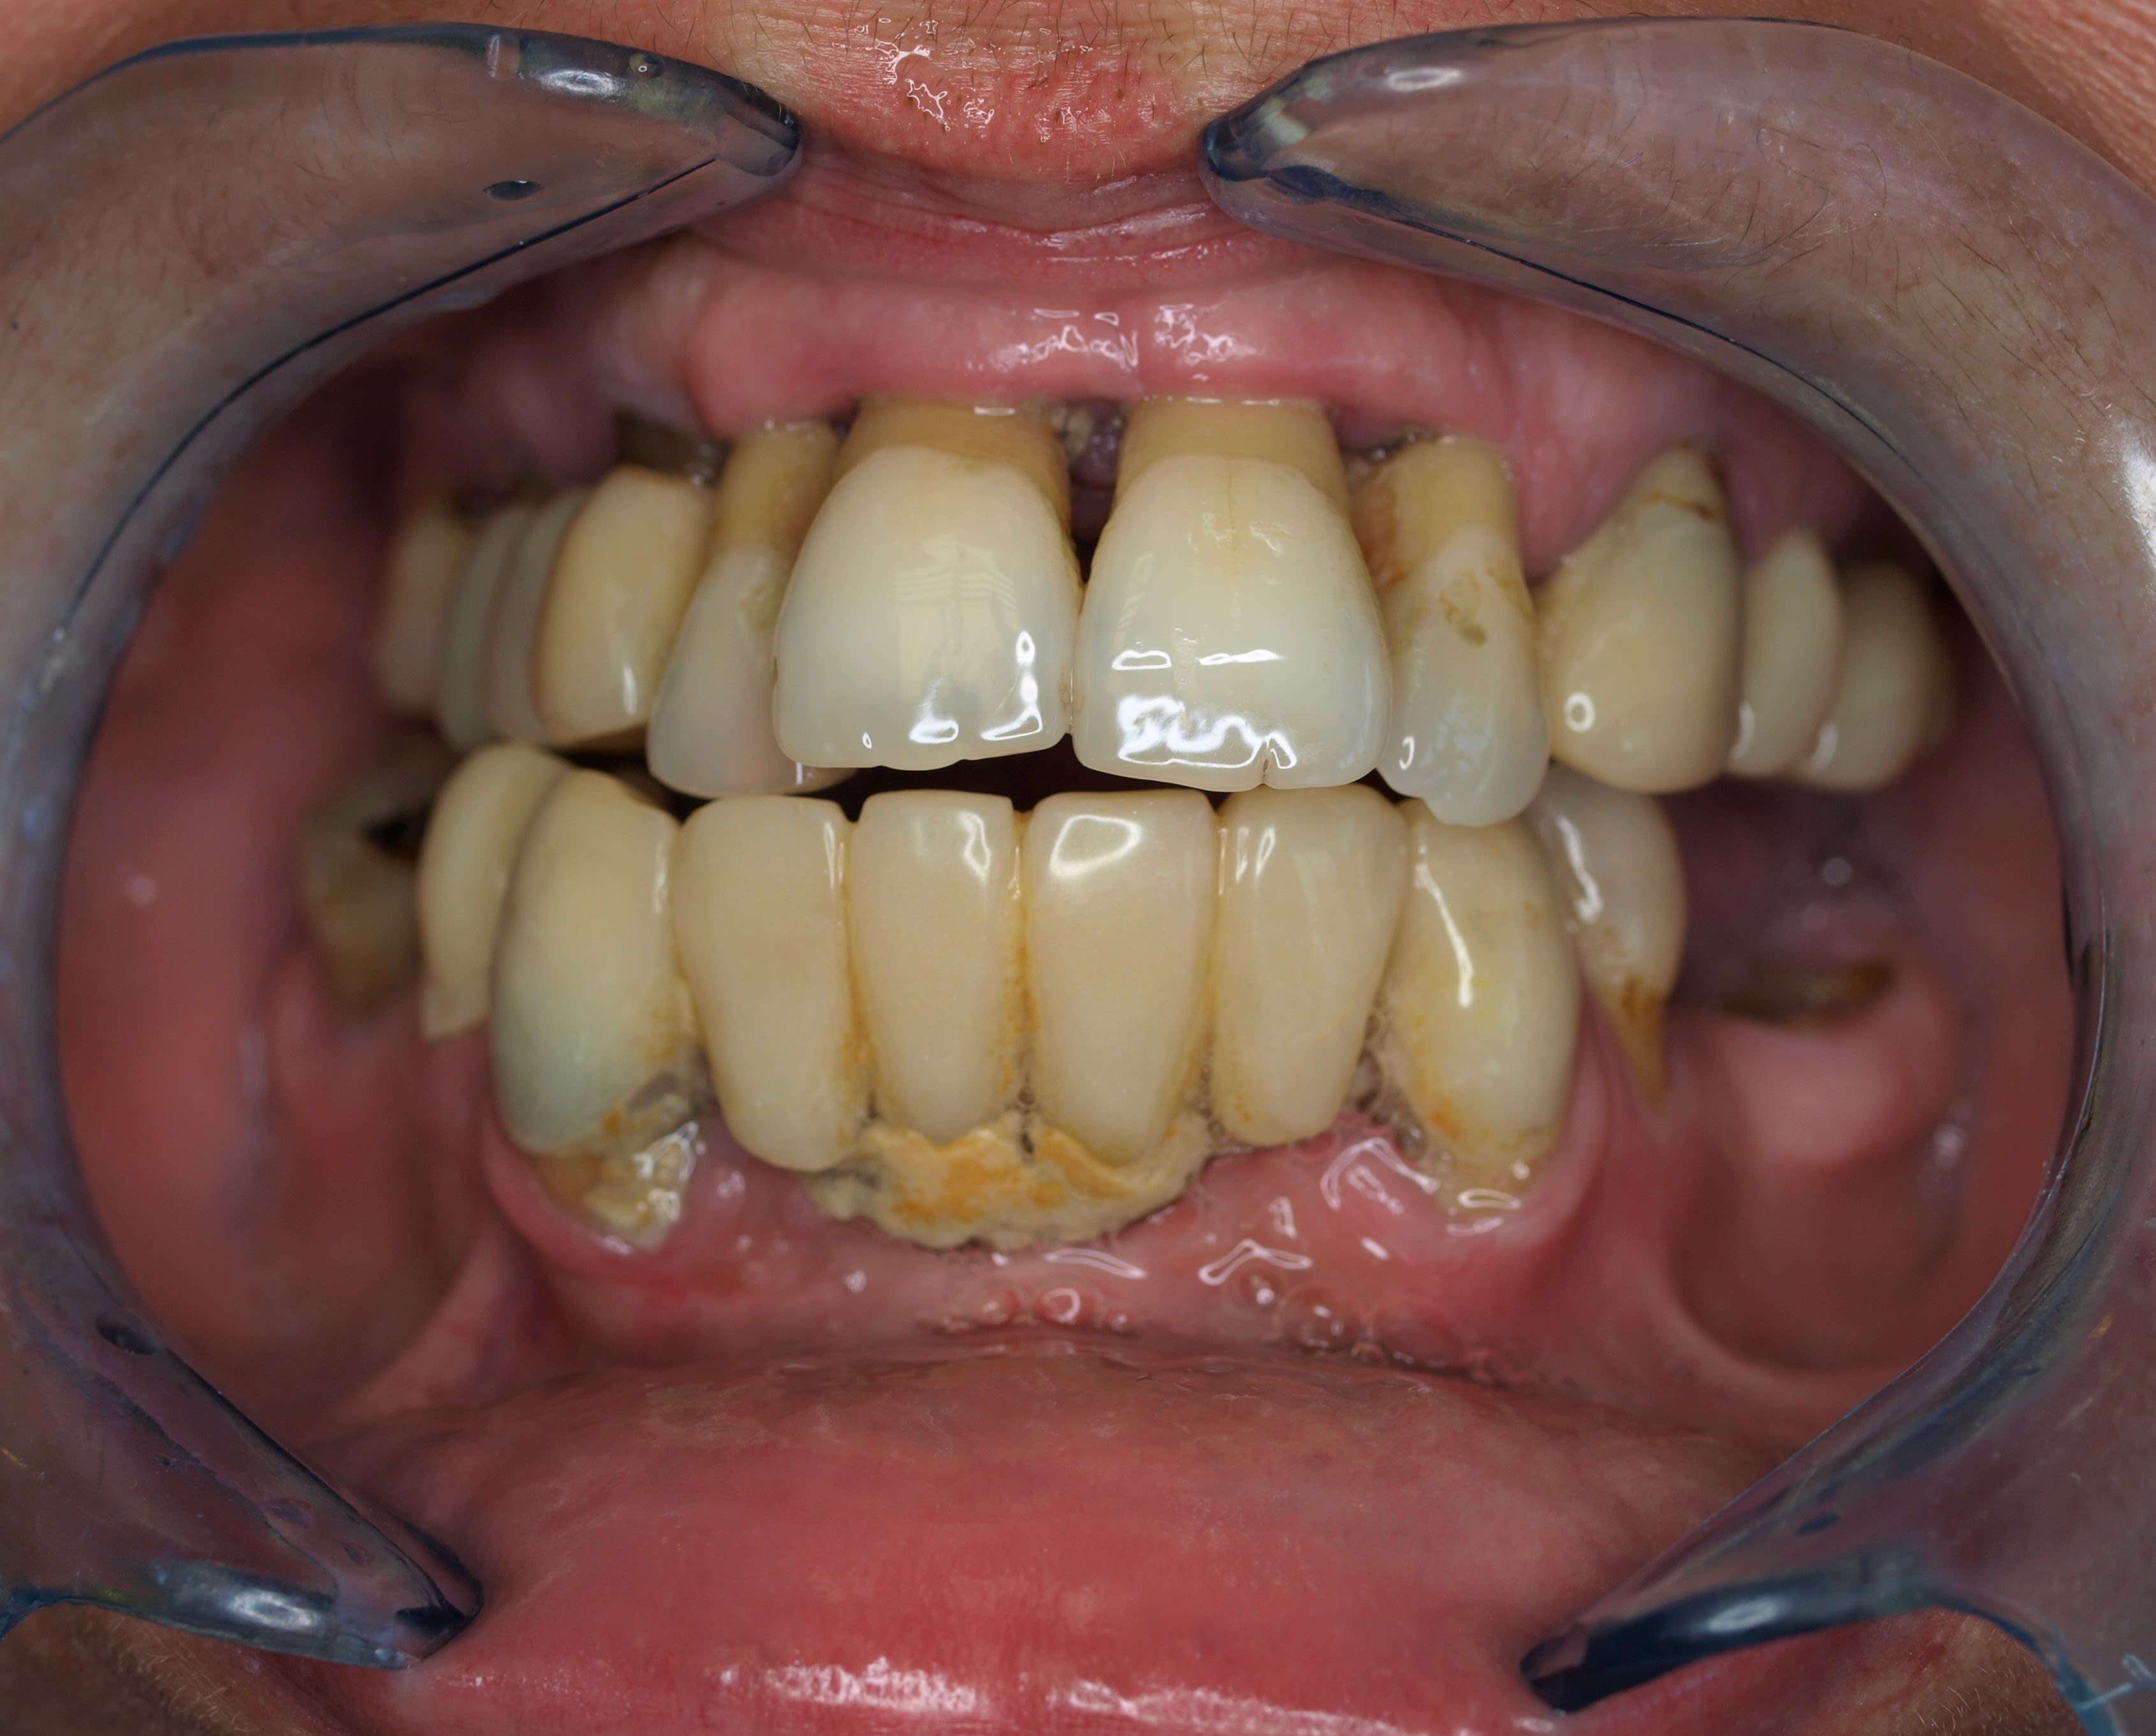

Mise_en_charge_immédiate_Positdental_R._004_zctmul.jpg

Mise_en_charge_immédiate_Positdental_R._005_b3jo3x.jpg

Mise_en_charge_immédiate_Positdental_R._006_ddh2n0.jpg

Mise_en_charge_immédiate_Positdental_R._001_hwwkac.jpg

Mise_en_charge_immédiate_Positdental_R._003_htglwg.jpg

Mise_en_charge_immédiate_Positdental_R._002_xkbebj.jpg